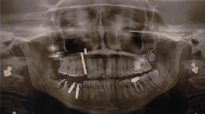

Figure 7: 5 zirconia implants placed in the 2nd and 3rd quadrant.